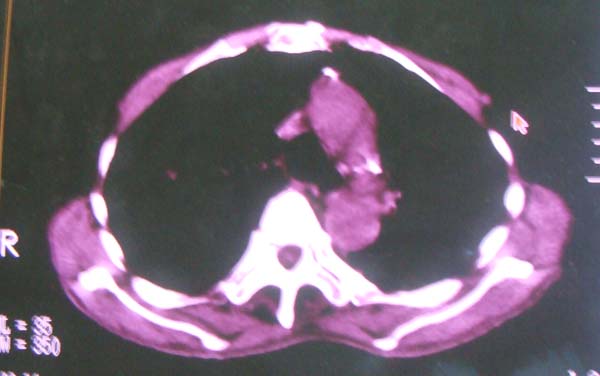

以下是引用zhangzhongshou在2008-2-15 22:25:00的发言:[br]片子照得不清,基本考虑1、细支气管肺泡癌2、亚急性血行播散型肺结核。请结合临床。片子细节显示不清,无法提供进一步意见。

以下是引用杀毒软件在2008-2-15 22:34:00的发言:[br]小叶中心性肺气肿。两肺弥漫性病变,肺泡微石病,过敏性肺炎,尘肺2期,特发性肺纤维化都有可能。[br]不象肺泡癌。